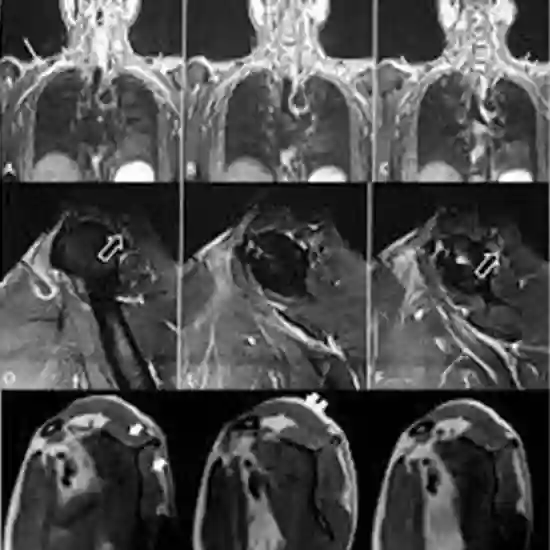

An MRI of the shoulder shows detailed pictures of the shoulder joint's bones, tendons, muscles, and blood vessels from any angle.

MRI (Magnetic Resonance Imaging) screening arm is a non-invasive medical diagnostic tool used to obtain detailed images of the left shoulder and the related tissue in the left shoulder. MRI Screening of the left shoulder is used to show abnormalities like fractures, injuries, and strains of the left shoulder.